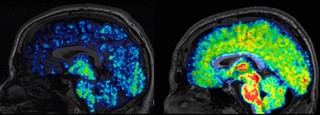

Factori circulanţi din sânge pot influenţa patologia Alzheimer; în studii preclinice, sângele tânăr a avut efecte protectoare împotriva boliiastăzi, 15:05